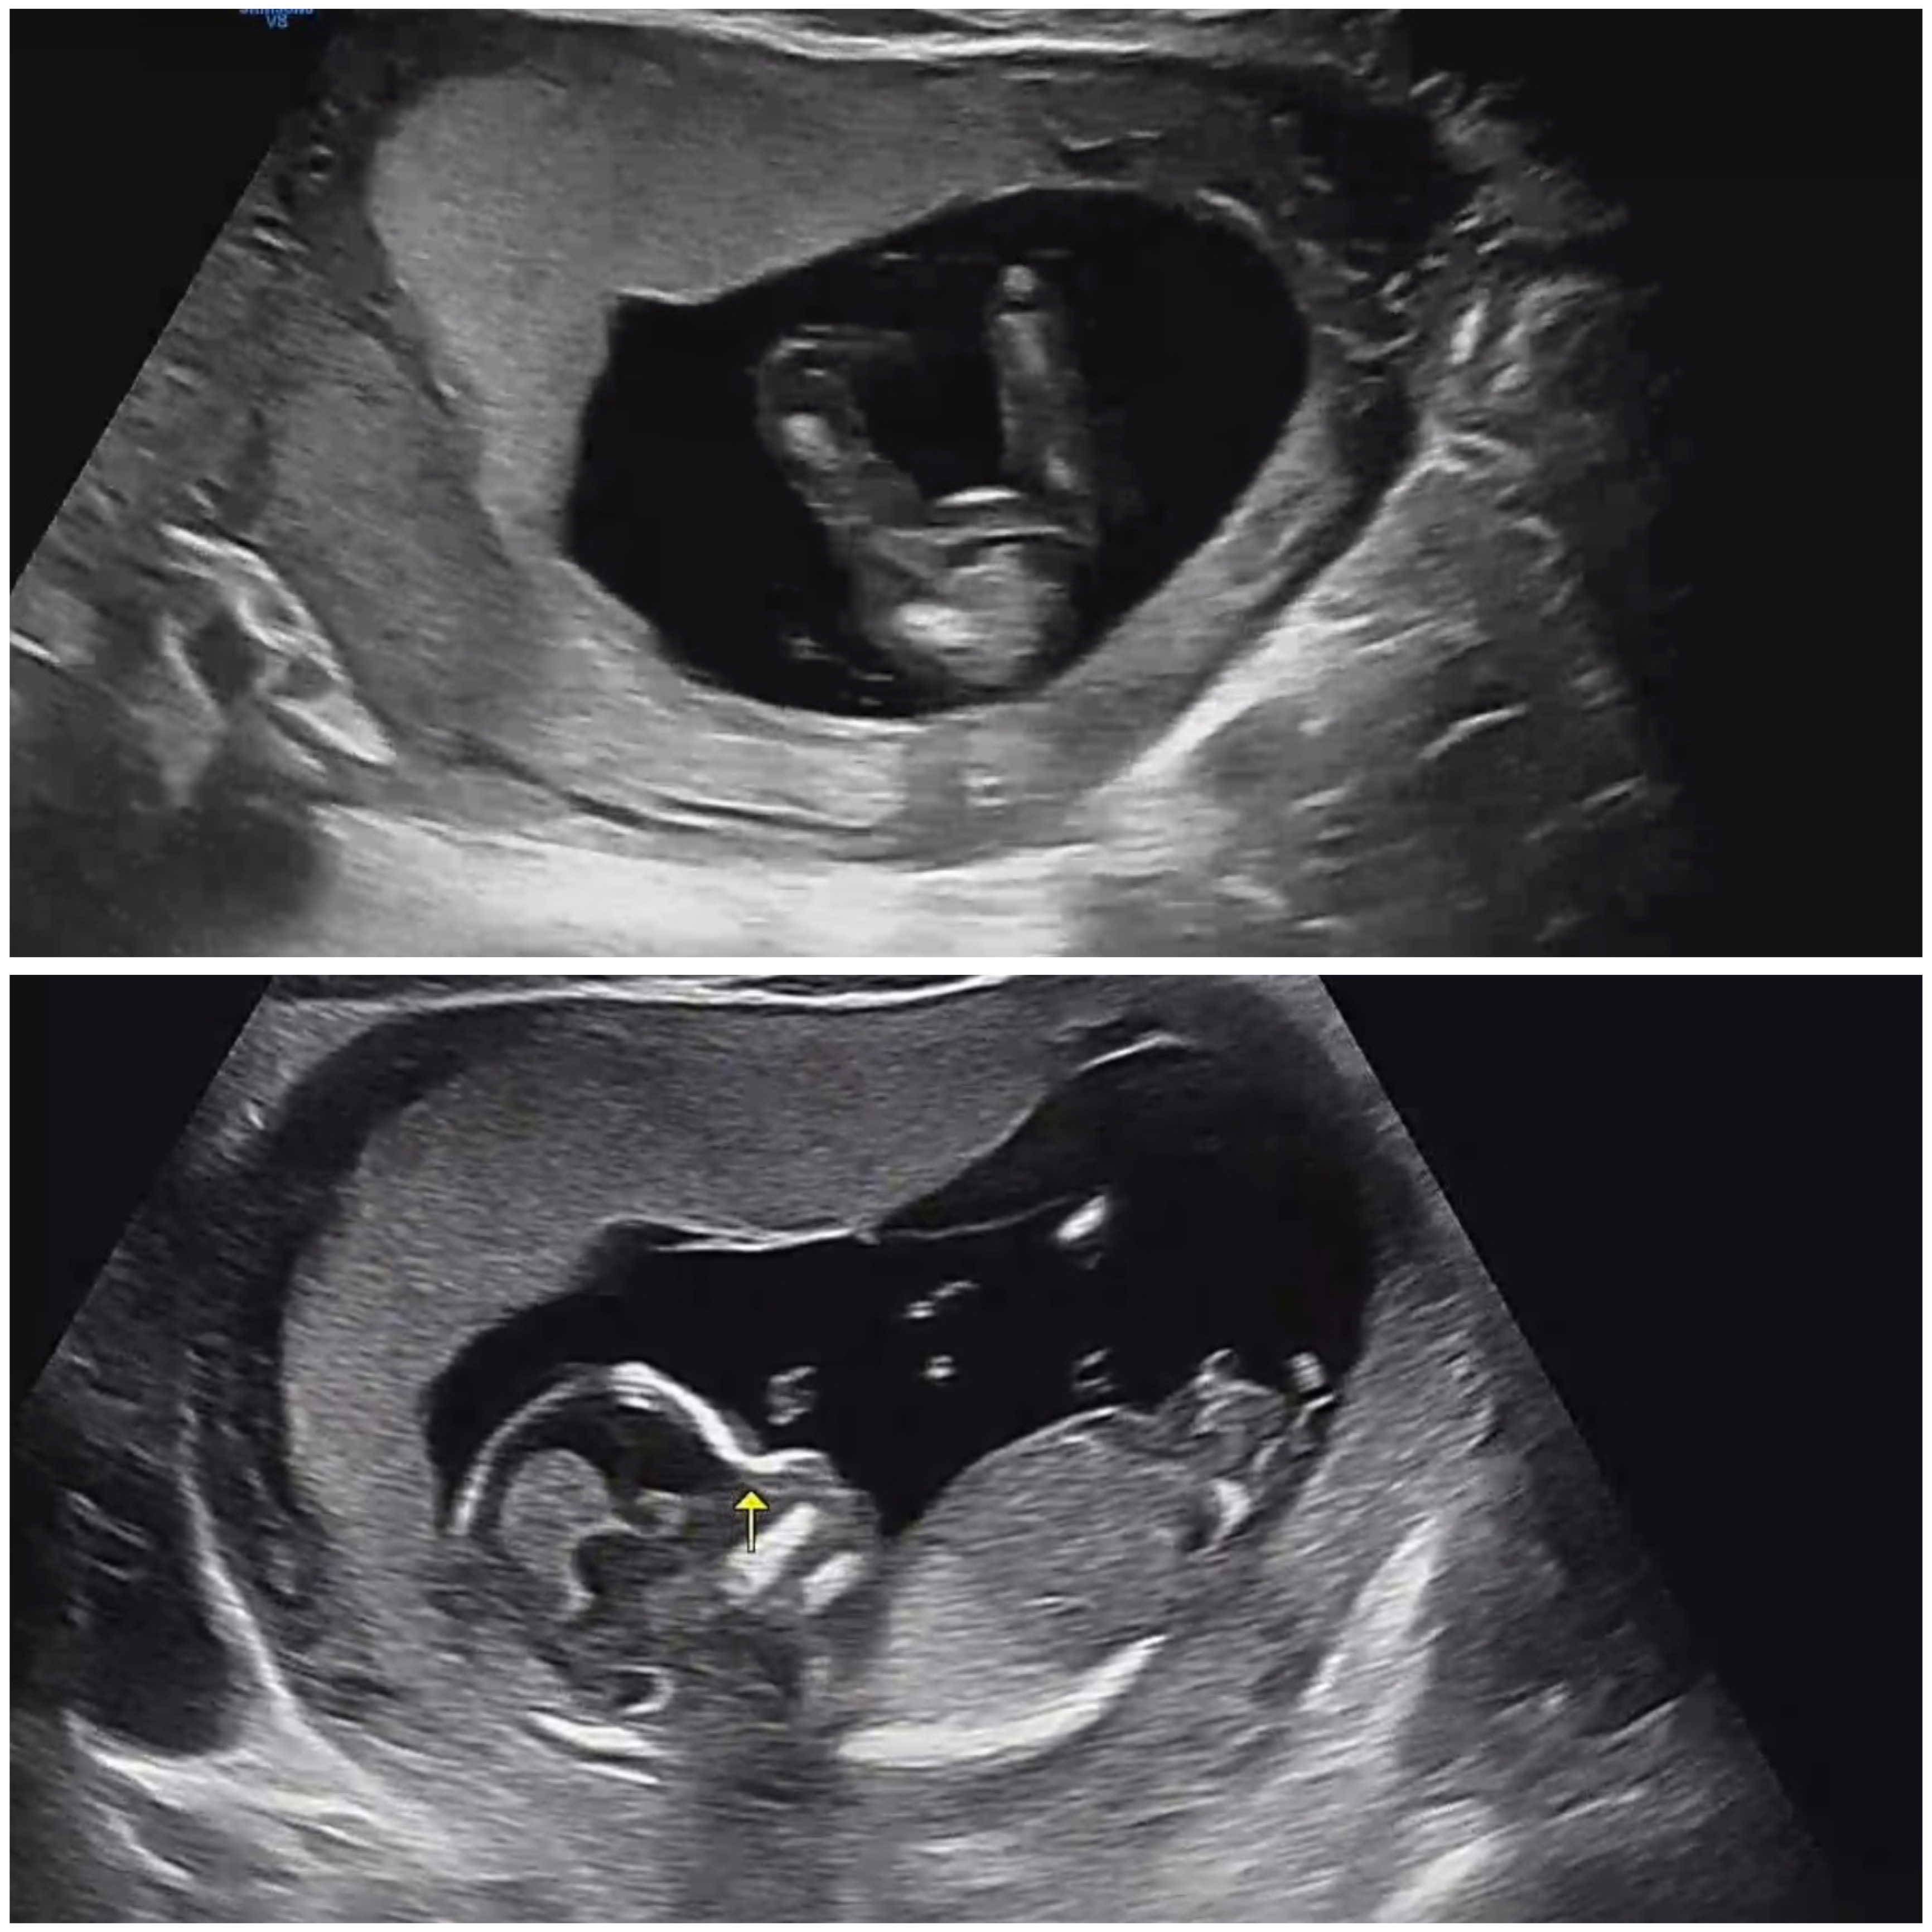

성별 반전 없겠죠?

안녕하세요 ~ 13주2일에 본 초음파 사진이고, 원장님은 딸이라고 확신하시더라구요(제가 주수 지나면 또 바뀔수 있는거 아니냐고 물어보니까 그럴일 없다고 하시더라구용..) 각도법도 딸인거 같은데 성별 반전 없겠죠..?

매우 매끈한게 공주님이네용 😚

16주에 반전 있는 분들도 있는데 저정도 매끈한거면 딸 맞을거 같아여!👏